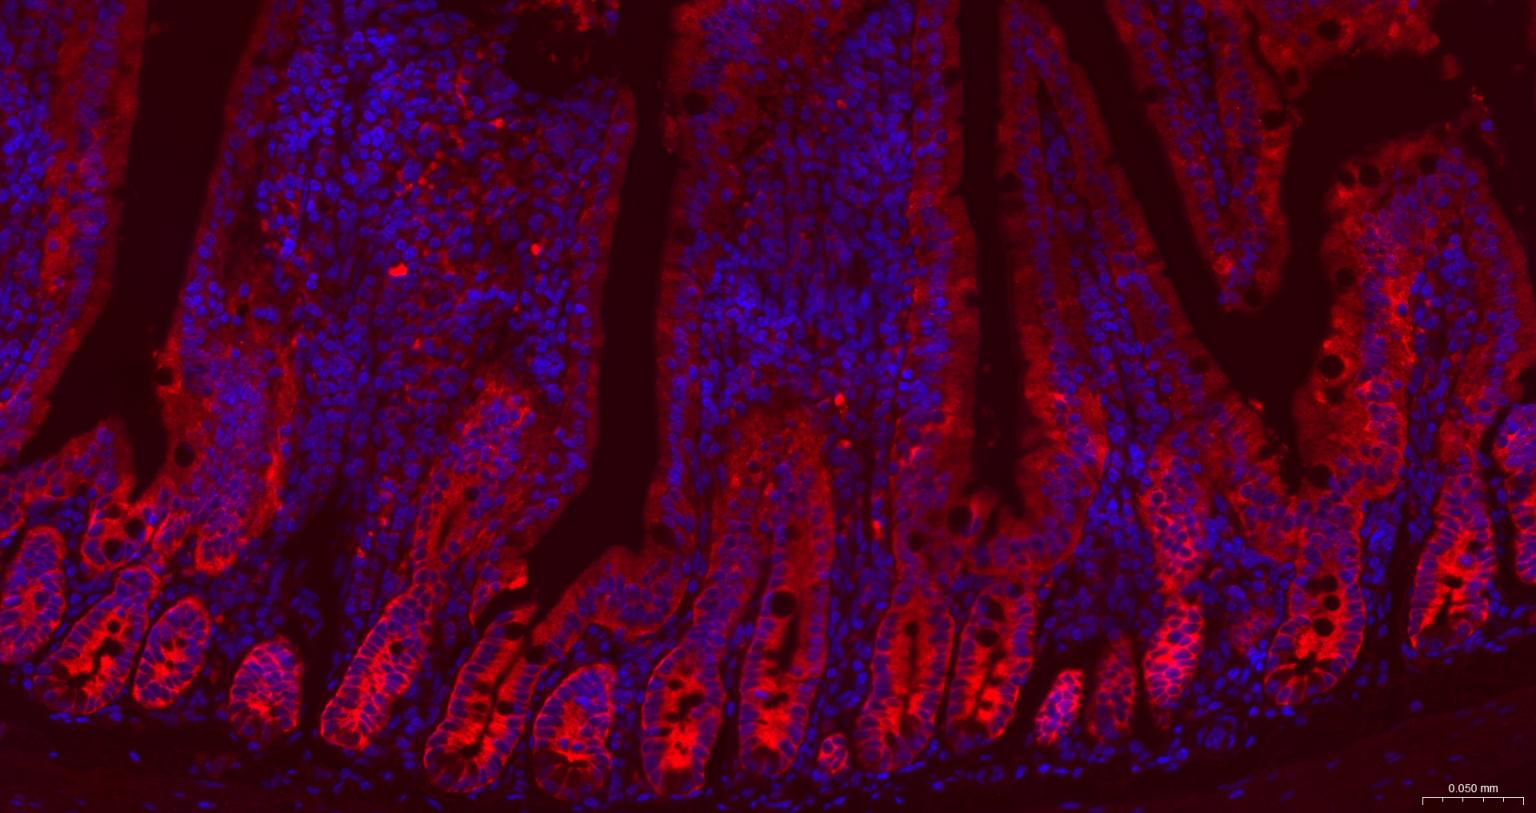

| IHC-F | Human, Mouse, Rat | 1:100-500 | |

| IF | Human, Mouse, Rat | 1:100-500 | |